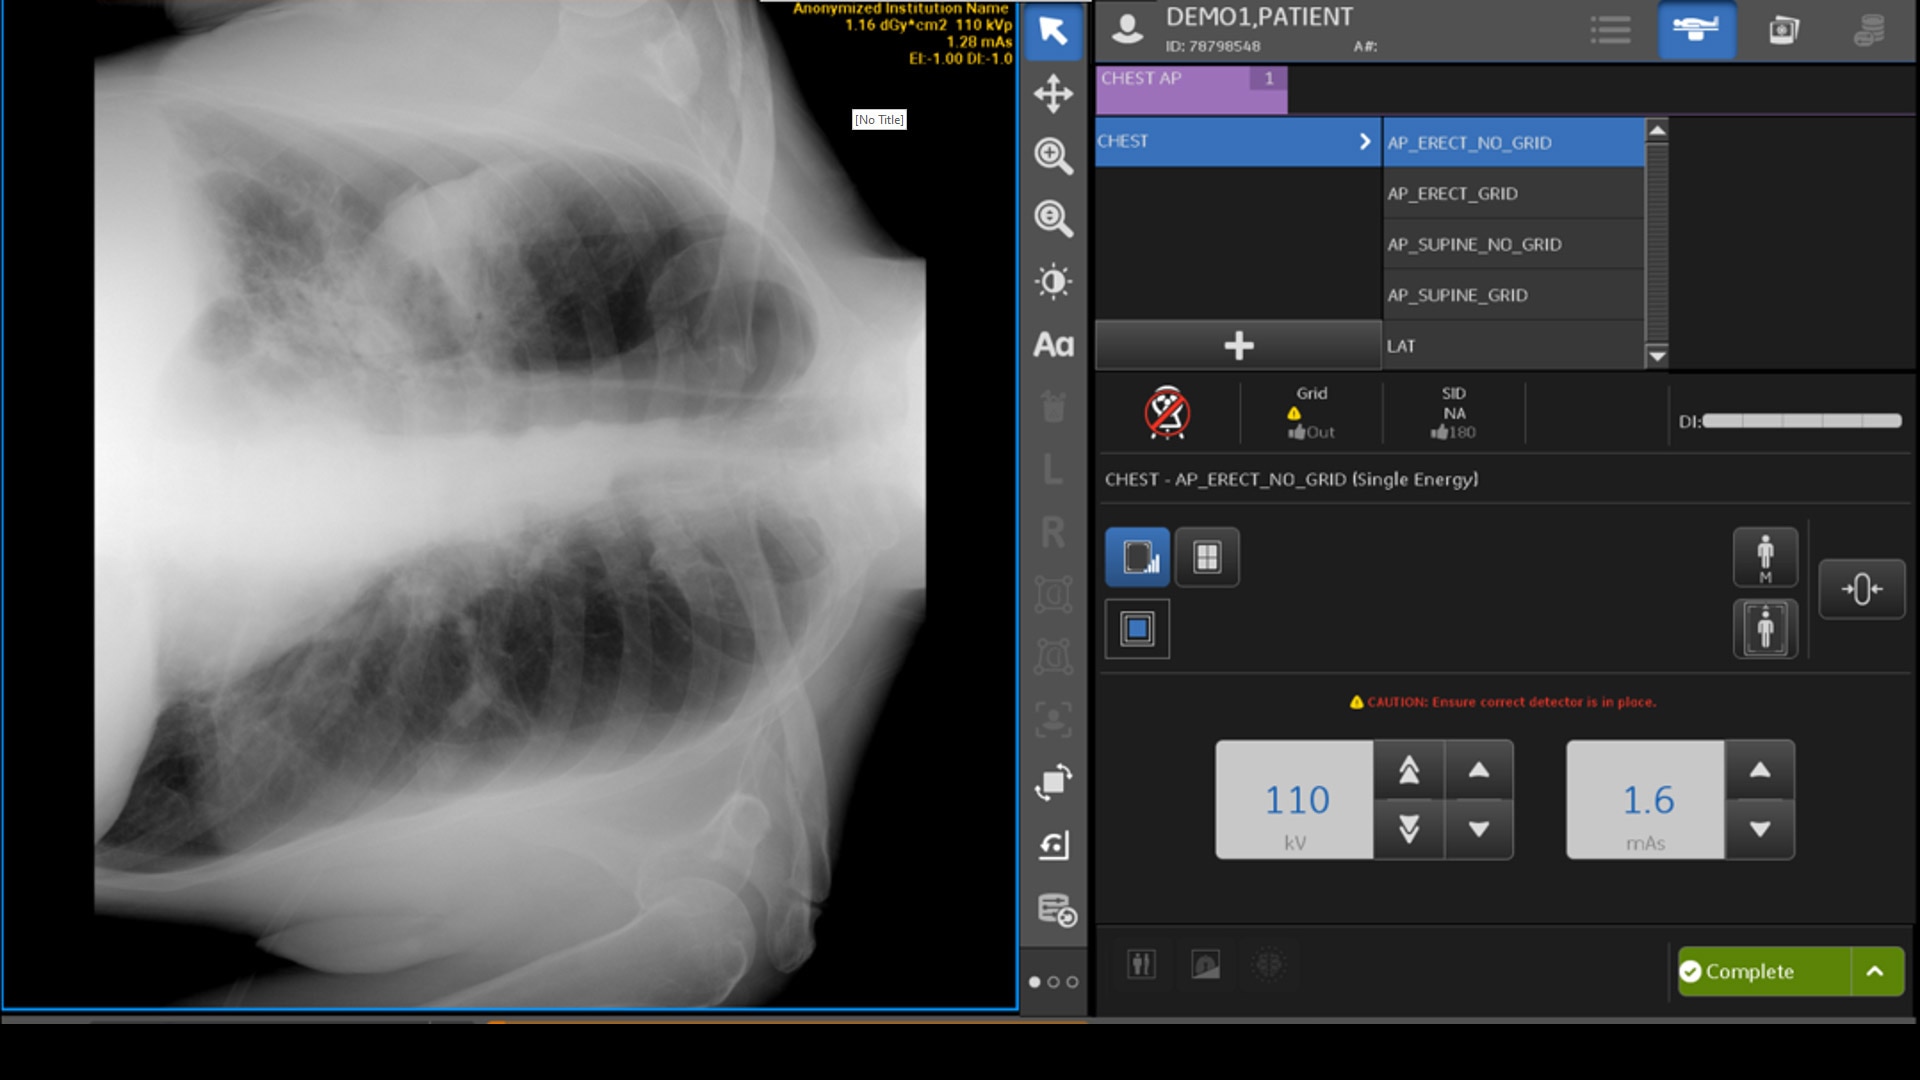

INTELLIGENT FIELD OF VIEW

AI that helps ensure a quality image

Intelligent Field of View detects when a lung field is clipped in a frontal chest X-ray (AUC >0.99) and notifies the technologist of positioning problems. This allows technologists to determine if a repeat is required before sending the image to PACS.2

Quality care-suite feature hero intelligent field of view